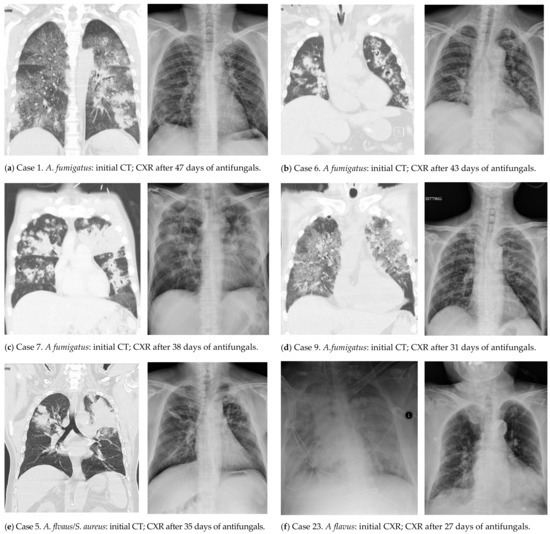

| 1 | 40+/M | CS, pancreatitis | B | 6 | 2.13 | nd | A. fumigatus | no | GGO, PBI, N, ws-C | VRC (5), CPF (5), VRC (36) | alive |

| 3 | 70+/M | PPU | B | 5 | 0.19 | 2.99/y | A. fumigatus | no | P | VRC (12), LAmB (15) | died (30) |

| 5 | 70+/M | CAD, CHF, DM | A (H1) | 0 | 0.36 | 3.16/n | A. flavus | SA | PBI, N, ws-C | VRC (51) | alive |

| 6 | 70+/M | CKD, COPD, MGUS | B | 4 | 4.26 | 5.07/n | A. fumigatus | no | PBI, N, cavities | VRC (51) | alive |

| 7 | 50+/M | DM | A (H3) | 6 | 0.71 | 5.25/n | A. fumigatus | no | GGO, PBI, N, cavities, ws-C | VRC (42) | alive |

| 9 | 70+/M | CHF, CS-E, HBV/LC, HCC, lymphoma | A (H3) | 1 | 0.09 | 2.44/n | A. fumigatus | no | GGO, PBI, N, ws-C | VRC (28) | alive |